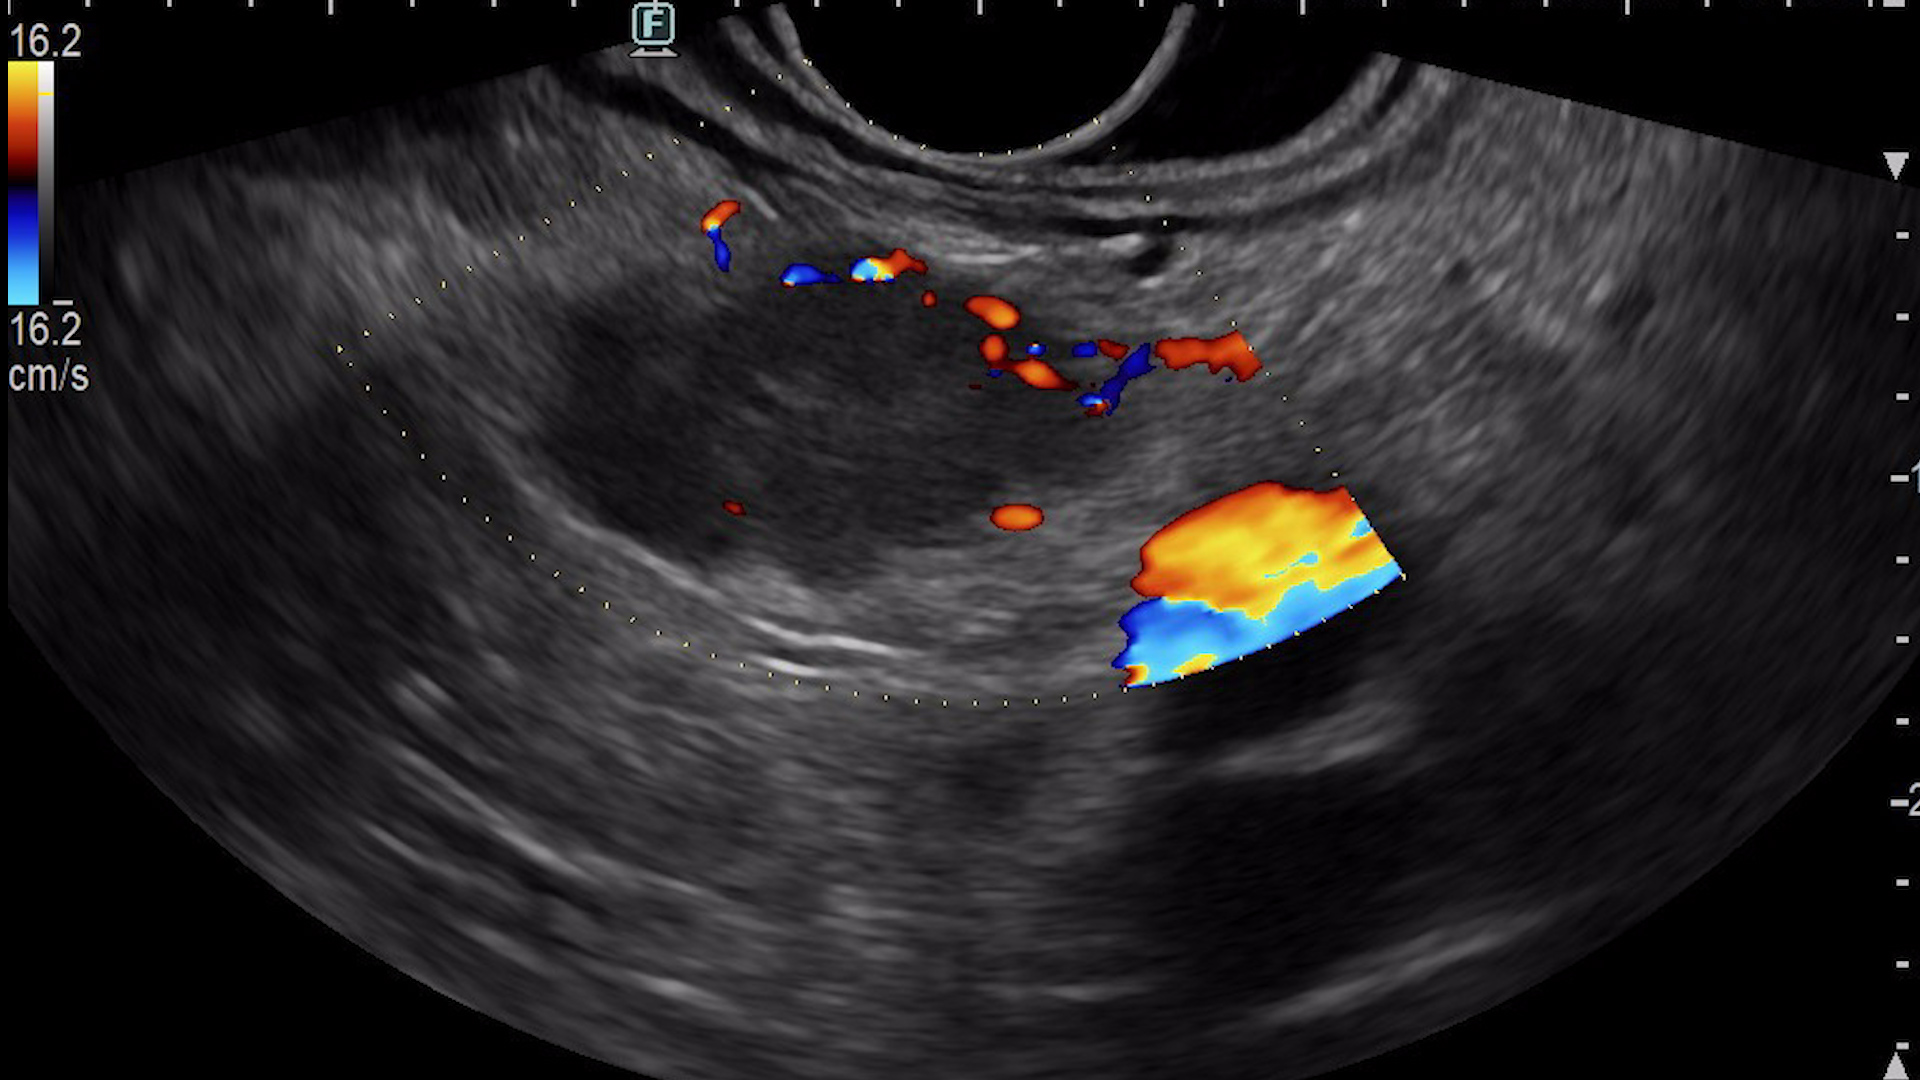

Consequently, an endoscopic ultrasound examination was carried out with tissue acquisition from the mass using a 22G Franssen-type needle (Acquire, Boston Scientific). The tumor was hypervascular on both color Doppler (Fig. 3a), detective flow imaging (Fig. 3b) and contrast-enhanced harmonic imaging (CHI) endoscopic ultrasound (Fig. 4). Histopathology was conclusive for a well-differentiated G1 neuroendocrine tumor, while immunohistochemistry confirmed the diagnosis, showing a Ki 67 index of 1%.